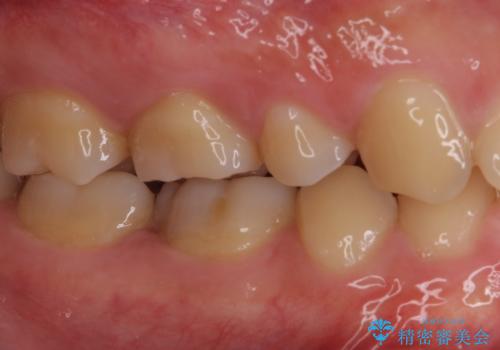

神経近くにまで及んだ大きなむし歯のセラミッククラウン

- 下顎左右奥歯に虫歯で痛みを感じるとのことで来院された患者様です。

むし歯が大きく、神経を取り除く可能性があることを理解いただいた上で虫歯を取り除き、その後はオールセラミッククラウンにて補綴することとしました。

虫歯除去後に痛みは収まり、神経も保存することができました。

変色していた歯もセラミッククラウンで自然な色合いとなり、患者様には大変満足していただきました。